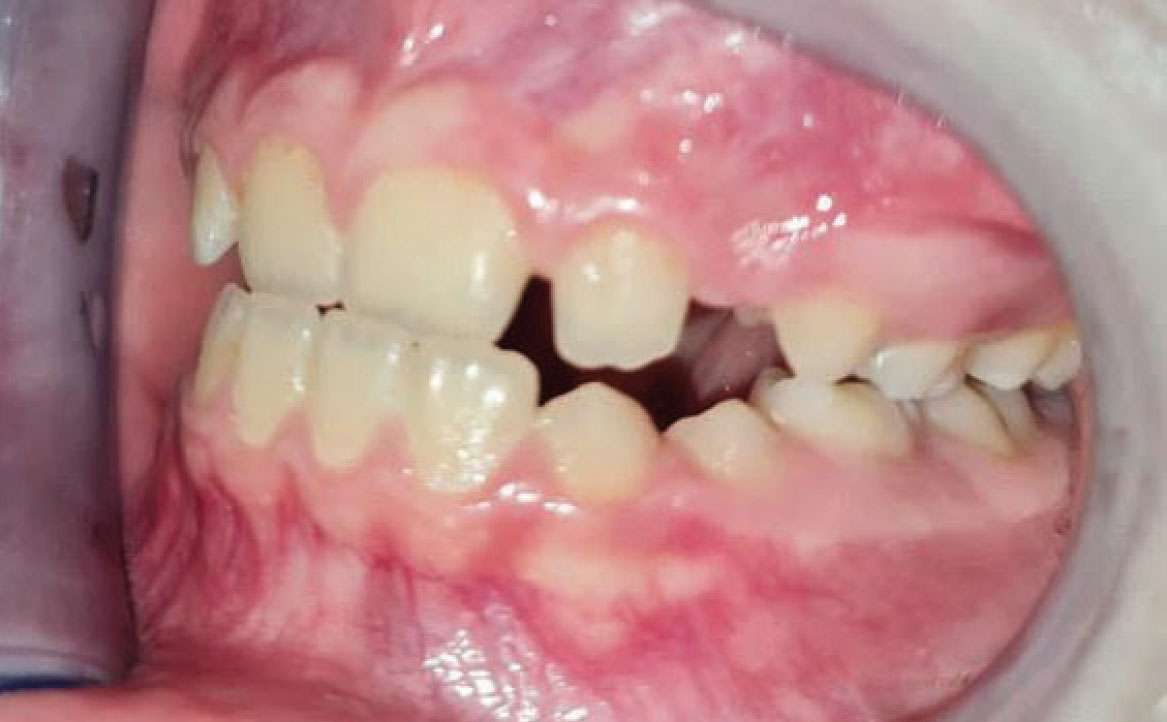

A livello intraorale sul piano sagittale è osservabile I classe molare destra e sinistra e classe canina non valutabile per mancanza degli elementi dentari durante la fase di permuta.

L’overjet e l’overbite sono entrambi ridotti in massima intercuspidazione. Trasversalmente il mascellare superiore è contratto (fig. 4-7).

Fig. 4A Foto intraorale in massima intercuspidazione.

Fig. 4B Foto intraorale in massima intercuspidazione.